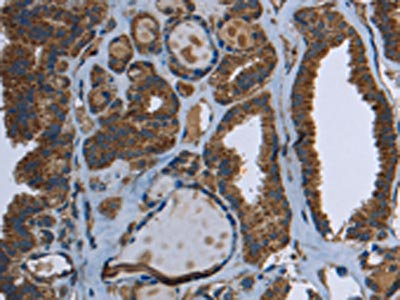

The image on the left is immunohistochemistry of paraffin-embedded Human thyroid cancer tissue using CSB-PA138466(GCK Antibody) at dilution 1/40, on the right is treated with fusion protein. (Original magnification: ×200)